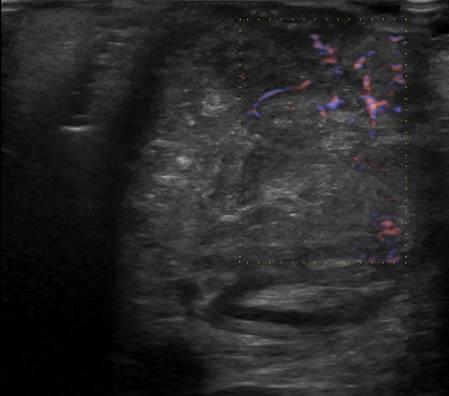

U tuyến nước bọt

» Thông tin: Nam giới – 79 tuổi.

» Lâm sàng: Khối vùng mang tai / K thực quản.

# Di căn tuyến nước bọt mang tai.